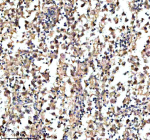

IHC analysis of KCNA6 using anti-KCNA6 antibody. KCNA6 was detected in a paraffin-embedded section of human liver cancer tissue. Heat mediated antigen retrieval was performed in EDTA buffer (pH 8.0, epitope retrieval solution). The tissue section was blocked with 10% goat serum. The tissue section was then incubated with 2 ug/ml rabbit anti-KCNA6 antibody overnight at 4oC. Peroxidase Conjugated Goat Anti-rabbit IgG was used as secondary antibody and incubated for 30 minutes at 37oC. The tissue section was developed using an HRP secondary and DAB substrate.